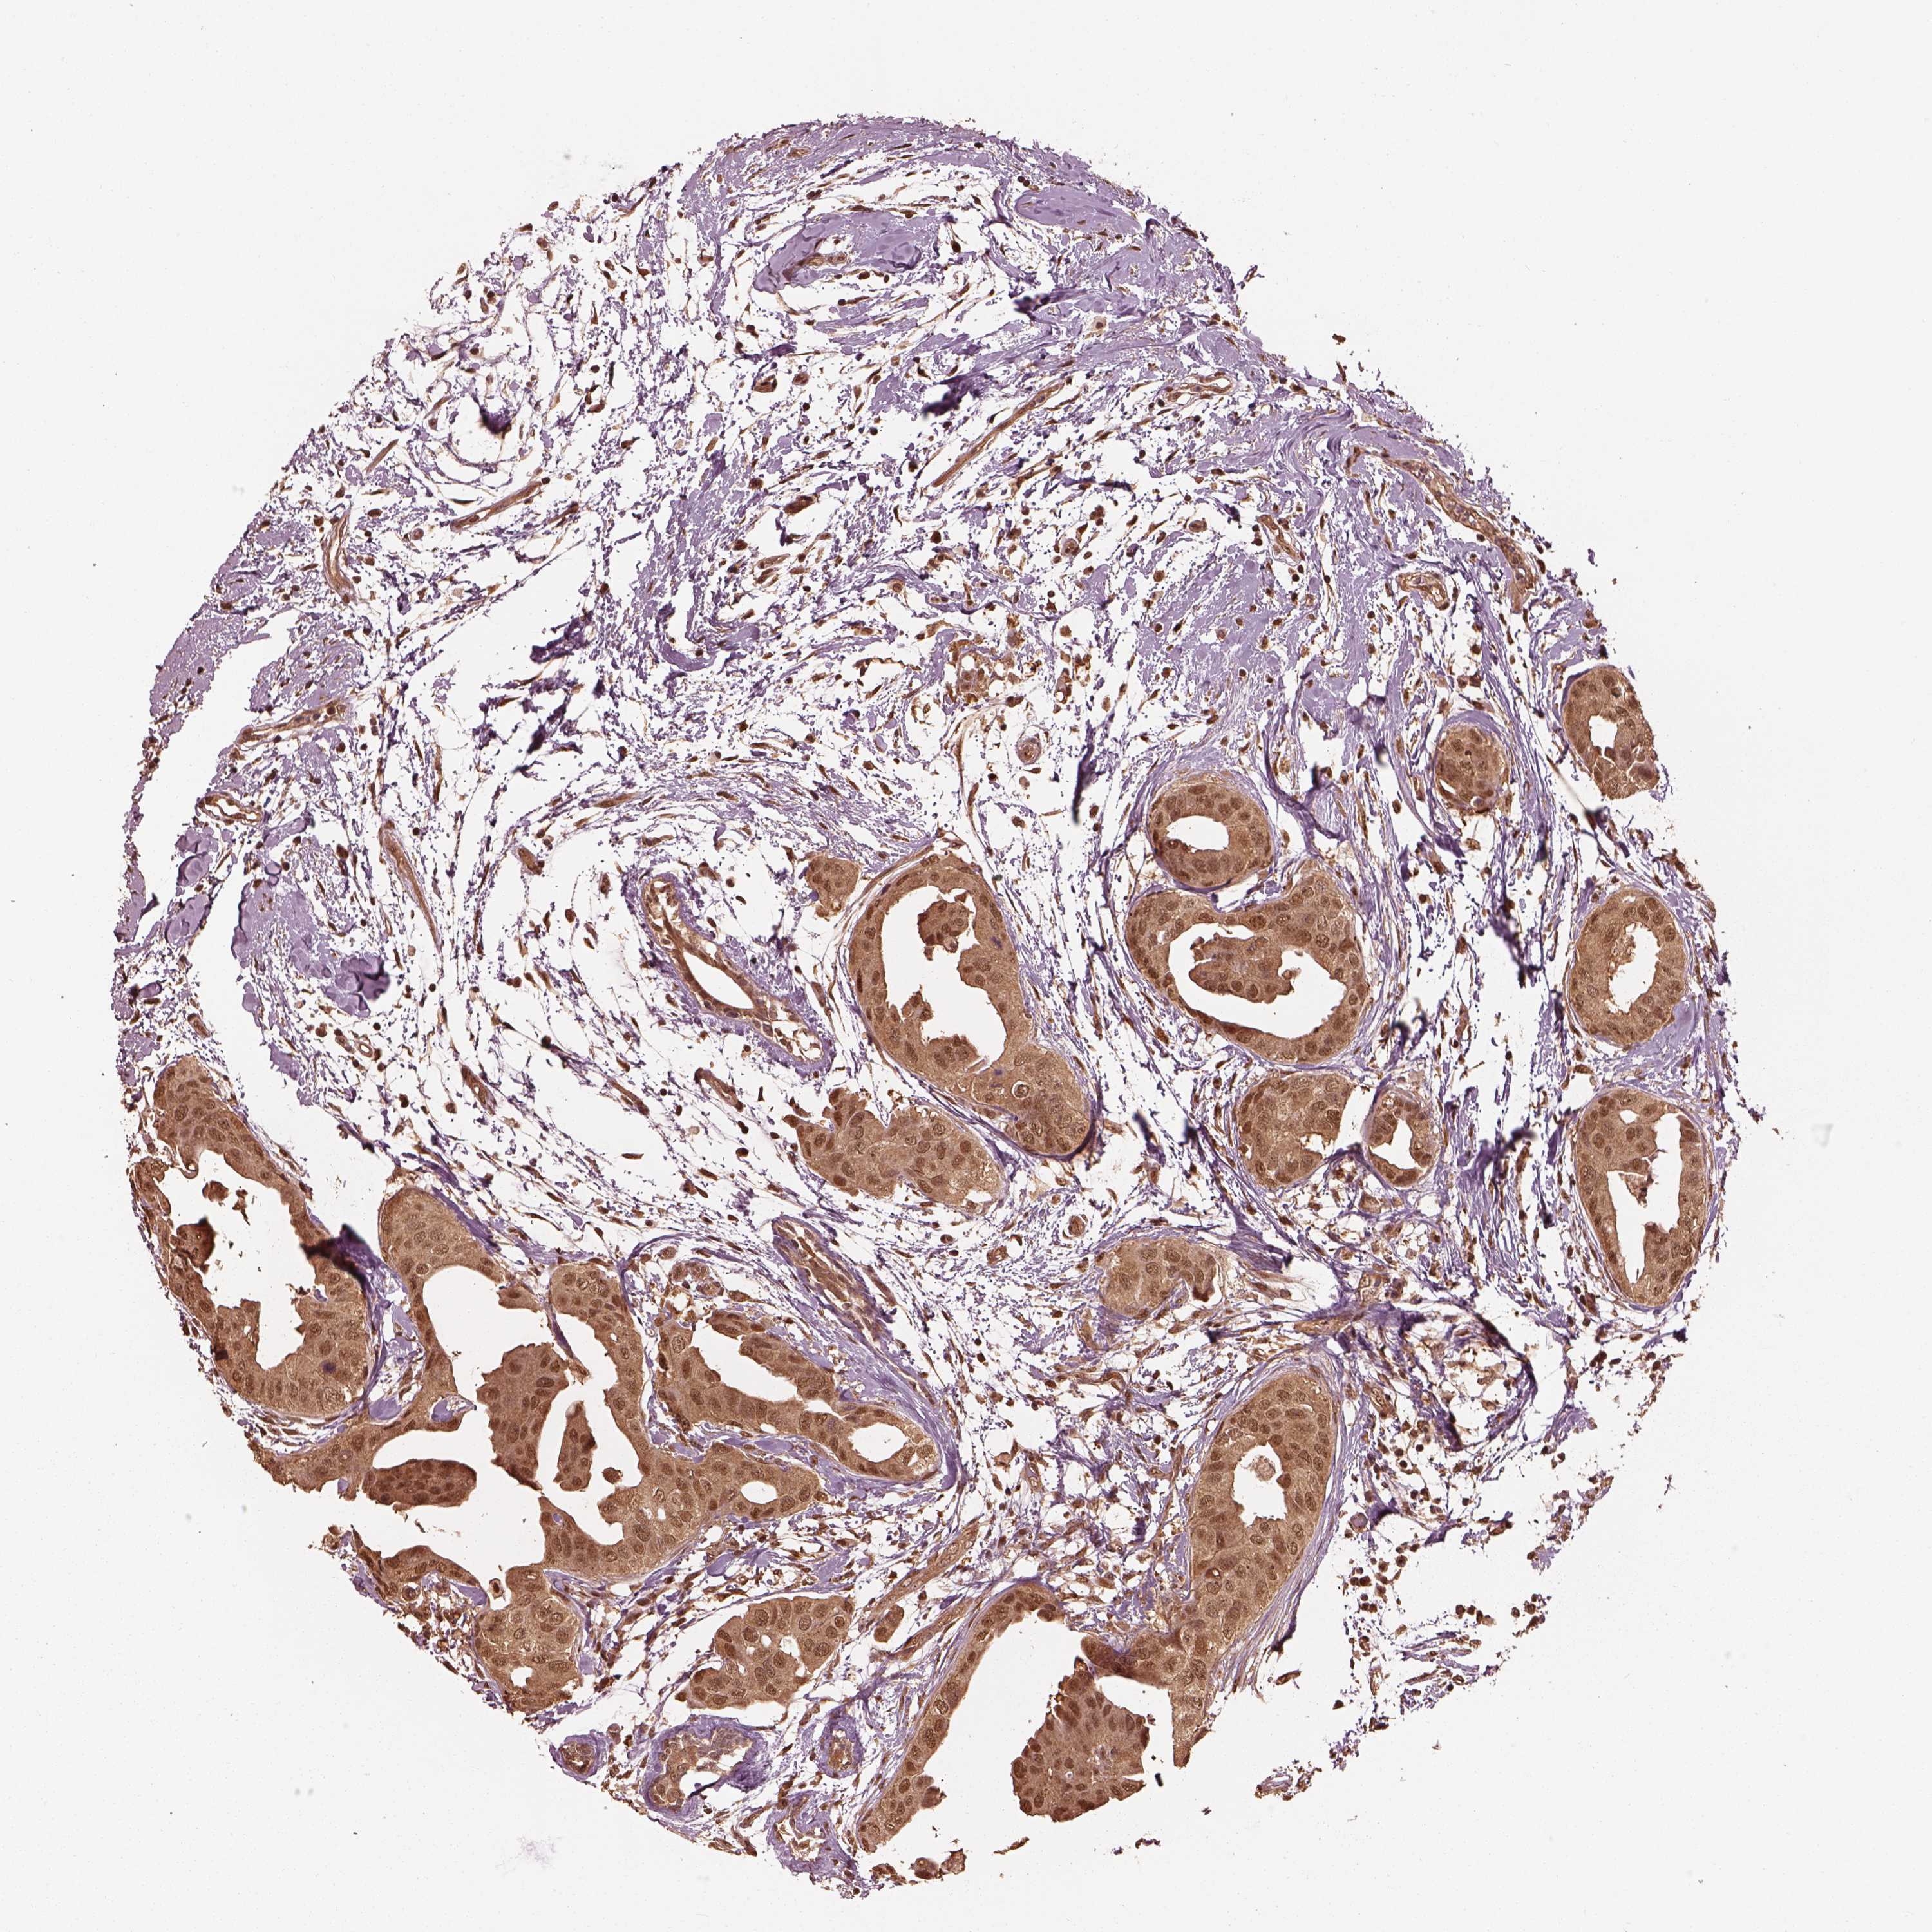

CANCER BREAST CANCER Show tissue menu

BRCA TCGA BRCA VALIDATION PROTEIN EXPRESSION